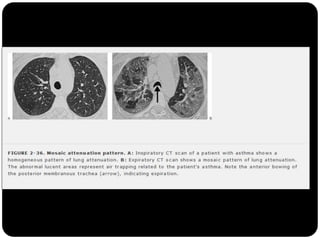

Perfusão em mosaico ( X vidro fosco)